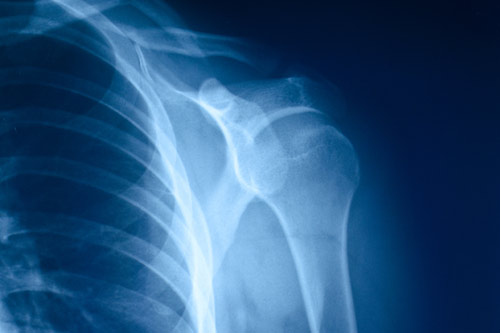

Los equipos radiológicos de adquisición de imagen sobre los que hacemos informes son:

- Radiología simple (CT y CR)

- Resonancia Magnética (RM)

- Tomografía Computarizada (TAC)

- Tomografía por emisión de positrones (PET) y

- Mamografías.